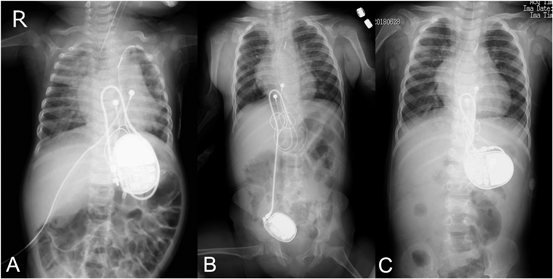

A 10-month-old female infant underwent an epicardial single chamber pacemaker implantation due to post-operative complete heart block following repair for ostium secundum type atrial septal defect (ASD). The patient was a monochorionic-diamniotic twin born at 24 weeks 5 days gestational age with a birthweight of 378 g. The pregnancy was complicated with twin-to-twin transfusion syndrome and postnatally she was managed at the referring neonatal center. She had pulmonary hypertension secondary to chronic lung disease, and remained on mechanical ventilatory support and continuous infusion of epoprostenol. She was transferred to our center for consideration of ASD closure and the surgery was performed at 10-months of age at a bodyweight of 3.0 kg. The patient developed post-operative complete heart block which did not resolve and an epicardial pacemaker implantation was performed one month post surgery. The pacing lead (4968 CapSure Epi 4968, Medtronic) was fixed to the right ventricular epicardium and the generator (Adapta SR ADSR01, Medtronic). The size of the generator was 42.9 mm in height, 40.2 mm in width, and 7.5 mm in thickness. The volume was 9.7 mL, and the weight was 21.5 g. A pocket was created under the left side of the rectus muscle, just above the posterior sheath (Fig. 1A). A part of the posterior sheath was torn because it was very fragile and thin because the patient was very small. It was very difficult to suture the torn posterior sheath. She was transferred back to the referring neonatal center 10 days post device implantation and received ongoing care until 20 months of age. Multiple complications included chronic lung disease, cerebral ventricular enlargement, optic nerve hypoplasia, retinopathy, and panhypopituitarism. She also continued to have frequent episodes of vomits which was thought to be secondary to gastroesophageal reflux. She returned to the outpatient clinic for her first routine pacemaker interrogation at 22 months. The device could not be detected by the programmer head at the original position and was noted to be in the pelvic region. An abdominal X-ray confirmed the migration of the device into the pelvic space (Fig. 1B). Although there appeared to be traction of the lead due to the generator dislocation, the lead continued to show stable thresholds at 1.25 V at 0.4 msec pulse width. In retrospect, previous X-rays performed at the referring center demonstrated migration, however this finding remained unnoticed. Given the risk of potentially life-threatening complications, the decision was to perform a generator reimplantation. An intraperitoneal migration of the device into the Douglas cavity was discovered, with a defect in the peritoneum. The generator pocket was once again created between the posterior sheath of the rectus muscle and left border of the rectus muscle and was further sutured to the posterior sheath (Fig. 1C). The perioperative course was uneventful and the patient was discharged from hospital 5 days post-surgical reimplantation. Since reimplantation of the device, her symptoms of vomits have completely resolved and the patient remains asymptomatic after a follow-up period of 6 months. Cardiac function of the patient was preserved through the course.